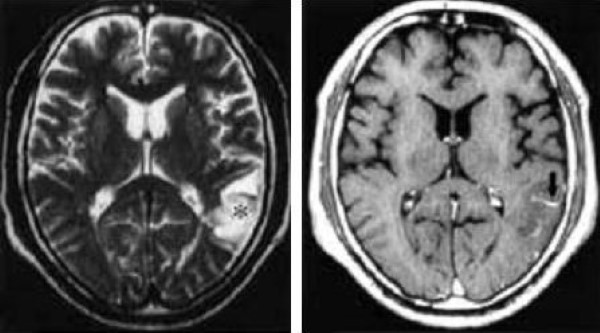

U mạch hang (cavernous angioma, CA) là một dị dạng mạch não. U mạch hang là một tổn thương giống khối choán chỗ với hiệu ứng khối rất ít hoặc không có, và đôi khi chảy máu trong u. U mạch hang xuất hiện là tổn thương tăng tỷ trọng, ranh giới không rõ, ngấm thuốc yếu trên CT. U thần kinh đệm có vôi hoá (calcified glioma) là một cân nhắc trong chẩn đoán phân biệt với u mạch hang, chụp MRI hữu ích cho mục đích phân biệt này (Hình 7). Mặc dù diễn biến lâm sàng và hình thái MRI của u mạch hang có thể giả u chảy máu [15], hình thái MRI điển hình của u mạch hang có tính chất đặc trưng, biểu hiện một lõi trung tâm hình mắt lưới, cường độ tăng hỗn hợp, được bao quanh bởi một vòng cường độ thấp biểu thị của lắng đọng hemosiderin.

Hình 7 a/b/c. Calcified glioma hay u chảu máu? Bệnh nhân nữ 20 tuổi biểu hiện liệt mặt phải đột ngột. (Chẩn đoán mô bệnh học: cavernous angioma có chảy máu trong u).

a: chụp CT cho thấy một tổn thương tỷ trọng cao không đồng nhất với vùng giảm tỷ trọng bao quanh ở vùng dưới vỏ trung tâm bán cầu trái.

b và c: MRI. Cả hai ảnh SE T1-W (500/15) và FSE T2-W (3600/110) cho thấy sự trộn lẫn của nhiều nốt nhỏ cường độ cao và cường độ thấp trong tổn thương, đặc trưng của cavernous angioma. Phù bao quanh biểu hiện dưới dạng một vùng cường độ cao thay vì một viền cường độ thấp đặc trưng do chảy máu trong u (c).